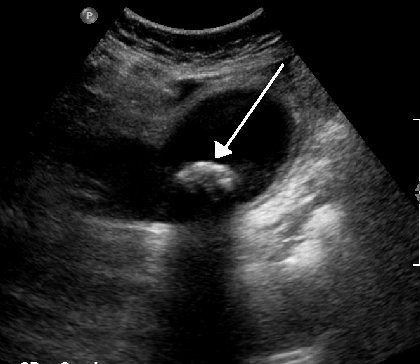

복부 초음파에서 가라앉는 담석은 대개 후방 음향 그림자를 갖는다. 뜨는 담석의 경우, 선근증이라고 하는 임상 상태에서 반향 에코(또는 혜성 꼬리 인공물)가 대신 보인다. 또 다른 징후는 담석의 특징이기도 한 벽-에코-그림자(WES) 삼중체(또는 이중 아크 그림자)이다.[28]

의료 초음파 검사에서 볼 수 있듯이 담낭 경부에 박혀 담낭염을 유발하는 1.9cm 담석. 담낭벽 비후는 4mm이다.